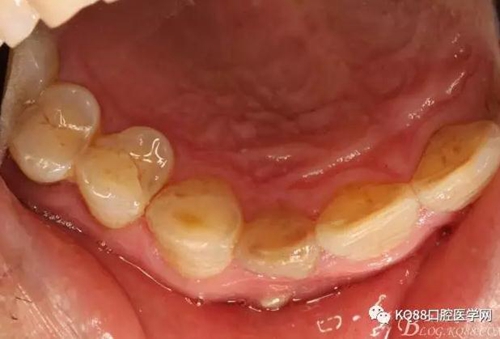

圖2. 12牙齒在我院進行熱牙膠根管充填+樹脂充填。

圖3.腭側(cè)觀;11腭側(cè)牙齦正常,21腭側(cè)樹脂充填完好